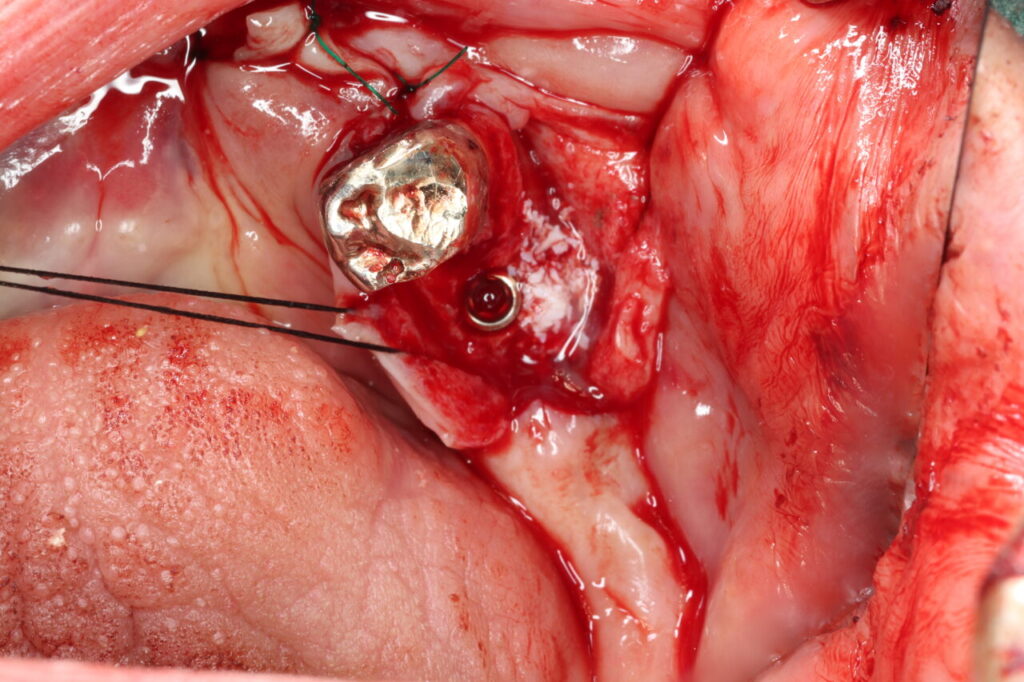

術中写真。骨の足りないところは骨増生を行い、将来的な顎骨の吸収を補うことでインプラント体を長持ちさせます。4本のインプラントを埋入しました。